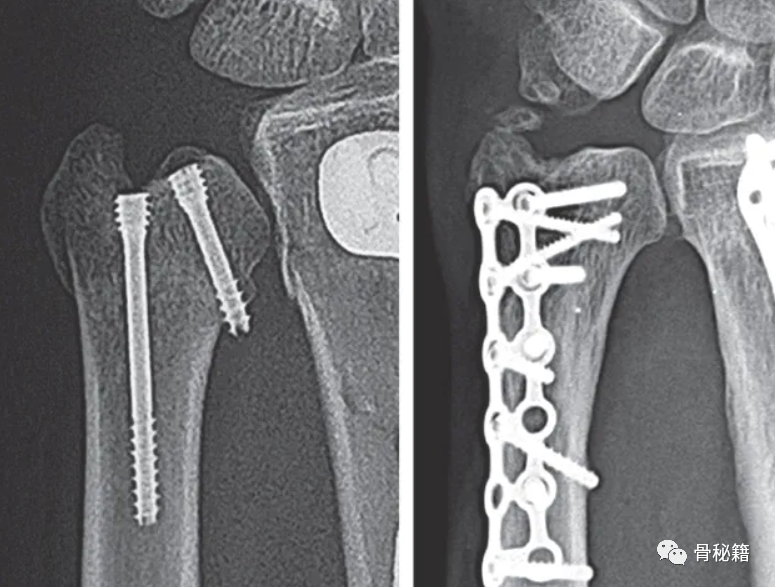

目前最常见的固定方式为:空心螺钉与钢板固定,克氏针等

3 对于近端和比较复杂的骨折,建议采用钢板固定,这样可以带来相对较好的稳定性

最常用的是尺背侧入路